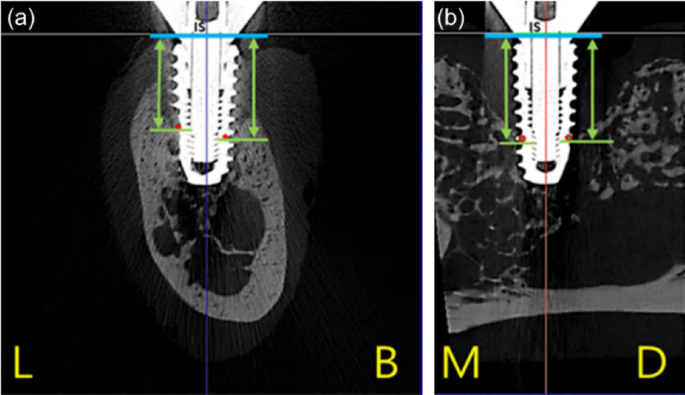

To analyze the pattern of peri-implant bone loss, four types of dimensions were measured from implant shoulder to the most coronal bone-to-implant contact in micro-CT sections. Distance calibration was performed using ImageJ version 1.53 for image processing and analysis for every radiograph to compensate for linear distortion. The following linear measurements were performed parallel to the long axis of each implant at four points: buccal, lingual, mesial, and distal sections (Fig. 5).

Peri-implant bone loss was evaluated by measuring linear dimensions in four directions from the implant shoulder to the most coronal point of surrounding bone attached implant threads on micro-CT cross sections: Buccolingual section (a) and mesiodistal section (b). (L: lingual, B: buccal, M: mesial, D: distal)